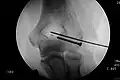

Kirschnerdraht

Die geschlossene Reposition und Fixierung einer Fraktur mittels eines rotierenden Bohrdrahtes (seit 1931[17] als Kirschner-Draht bezeichnet) ist – eingeführt in den 1920er-Jahren – eines der ältesten heute noch regelmäßig angewendeten Verfahren der operativen Frakturbehandlung. Als Materialien stehen Edelstahl und Reintitan zur Verfügung.

Sie wird eingesetzt als

- perkutane intramedulläre Schienung, zum Beispiel an den Mittelhandknochen

- perkutane „Spickung“, also Fixierung einer Fraktur durch Einbringen eines Kirschnerdrahtes, wenn möglich mit Fixierung des Drahtes in der gegenüberliegenden Kortikalis.

Aufgrund der Biegsamkeit der Drähte und der nicht formschlüssigen Verankerung der Drähte im Knochen ist das Operationsergebnis in der Regel nicht bewegungsstabil, sodass weitere Ruhigstellungsverfahren, z. B. Gipsverband oder auch der hier illustrierte Fixateur externe zur Anwendung kommen müssen.

Bei der hier dargestellten Handgelenkfraktur war eine bewegungsstabile Versorgung z. B. mittels winkelstabiler Platte (s. u.) aufgrund der hochgradigen Osteoporose und der erheblichen Weichteilschädigung nicht sinnvoll, daher erfolgte die geschlossene Reposition mit Kirschnerdraht-Fixierung und zusätzliche Ruhigstellung mit Fixateur externe. Eine Gipsruhigstellung wäre hier ebenfalls aufgrund der schlechten Weichteilverhältnisse nicht möglich gewesen.

Vorteil der Kirschnerdraht-Fixierung ist der geringe Verfahrensaufwand und die geringe Invasivität. Die Entfernung der Drähte erfolgt in der Regel unmittelbar nach Abschluss der Frakturheilung (also nach ca. 4 bis 6 Wochen).

Nachteil der Kirschnerdraht-Fixierung ist die Kombination der Risiken eines invasiven Eingriffes (Infektion, Narkoserisiko) mit den Nachteilen einer längeren Ruhigstellung (Muskelatrophie, Einsteifung des Gelenkes, keine frühfunktionelle Behandlung möglich).

Spezifische Komplikationen und Risiken sind „Wandern“ der Drähte, Drahtbruch und Korrekturverlust.